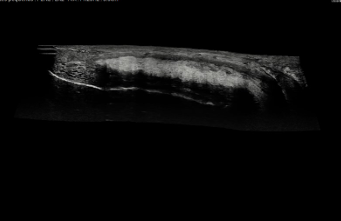

La fibrosis completa de los cuerpos cavernosos es una condición desafiante en el contexto de la cirugía de implantes de prótesis peneanas. Esta fibrosis severa limita la flexibilidad y funcionalidad de los cuerpos cavernosos, dificultando la colocación de prótesis y, en muchos casos, la restauración de una función eréctil satisfactoria. Para abordar esta patología, la literatura médica ha descrito diversas técnicas quirúrgicas avanzadas, cada una diseñada para mejorar la viabilidad de los implantes en un entorno de fibrosis extensa.

1. Excavación Corporal

La «excavación corporal» es una técnica clave que facilita la implantación de prótesis peneanas en pacientes con fibrosis severa de los cuerpos cavernosos. Este procedimiento consiste en remover el tejido fibroso dentro de los cuerpos cavernosos, creando el espacio necesario para la prótesis sin recurrir a injertos adicionales. Una ventaja significativa de esta técnica es su bajo índice de complicaciones, lo que la convierte en una opción viable para cirujanos experimentados en este tipo de procedimientostomía Óptica y Resección Transcorporal